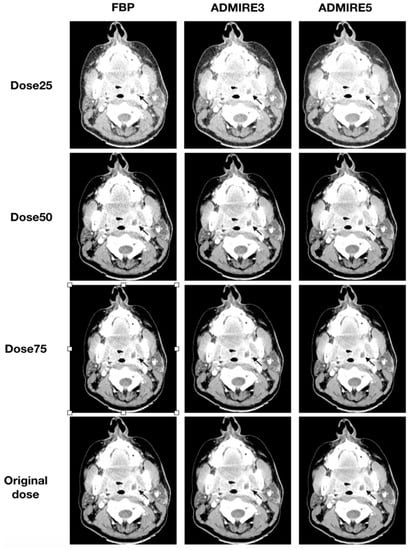

All 48 patients were analyzed for the presence of a neck abscess. A total of 35 abscesses were diagnosed in the original datasets. All three blinded readers had a sensitivity of 100% (95% CI: 88–100) and specificity of 100% (95% CI: 72–100) for all simulated low-dose datasets, which were iteratively reconstructed with ADMIRE 3 or ADMIRE 5. FBP datasets had a sensitivity of 100% (95% CI: 88–100) and a specificity of 100% (95% CI: 72–100) for a dose reduction to 50% of the original dose. Deviations were only found in FBP reconstructed datasets at a dose of 25% of the original dose. Illustrations of the different reconstructions at the respective dose levels are shown in Figure 5 and Figure 6.

Figure 6.

Axial tomographic slices of a 46 year old female patient with left-sided peritonsillar abscess (arrow). All images were reconstructed with FBP, ADMIRE 3, and ADMIRE 5 (from left to right) at 75%, 50%, and 25% dose reduction of the original dose. Reader 1 missed the abscess in reconstruction mode FBP at a dose of 25%.